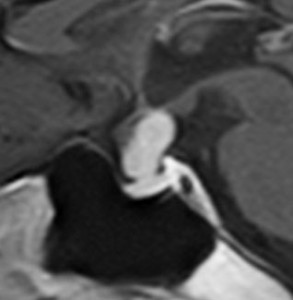

成人の下垂体柄に発生した小さな頭蓋咽頭腫です。のう胞性ですが石灰化もあり術前診断は可能でした。この頭蓋咽頭腫は,下垂体柄の内部から発生したものですから,下垂体柄が全周にわたってfunningしています。ちょうど前庭神経鞘腫における顔面神経のようなものです。また,冠状断で見ると下垂体柄が左に寄っているのが推測できますから,右側からアプローチします。腫瘍を観察しても,最初のうちは下垂体柄がどこにあるのかは解りません。